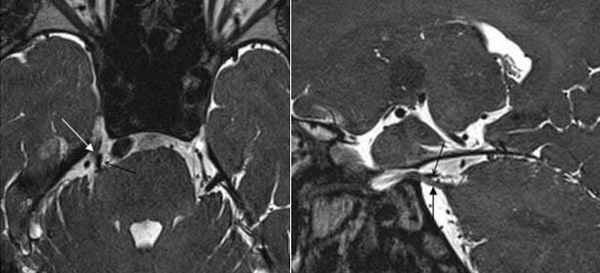

(Слева) При аксиальной МРТ CISS у пациента с левосторонним гемифациальным спазмом визуализируется петля левой позвоночной артерии, выдающаяся в цистерну ММУ, где она воздействует на проксимальную часть лицевого нерва в области выхода корешка.

(Справа) При аксиальной МРТ Т2 ВИ у пациента с гемифациальным спазмом определяется долихоэктазия позвоночной артерии, воздействующей на зону выхода корешка лицевого нерва во внутренних отделах цистерны ММУ. Приблизительно у 50% пациентов с гемифациальным спазмом обнаруживаются изменения на МРТ, обычно на тонкосрезовых Т2 последовательностях или МРА.